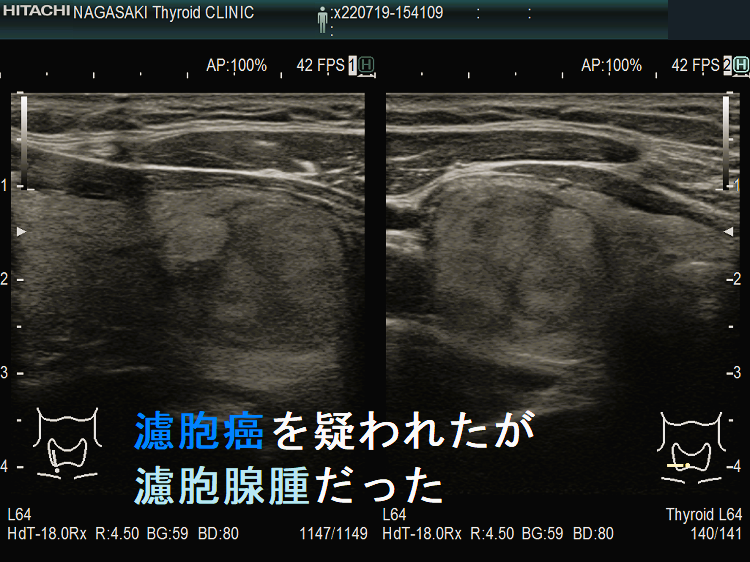

濾胞癌を疑われたが濾胞腺腫だった 超音波(エコー)画像;特に、中心部の極めて低エコーな箇所が疑わしい。。

実際、同じような見え方で甲状腺濾胞癌だったケースもあります(内部に低エコー領域が存在する甲状腺濾胞癌)。